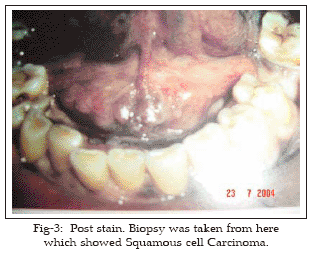

One hundred patients were included in the study and thirty out of them showed positive stain. Biopsy was taken from stained area.

Histology revealed squamous cell carcinoma in twelve patients and dysplasia in five, rest were negative for squamous cell carcinoma or dysplasia. Those who showed positive stain but were negative on histopathology for squamous cell carcinoma or dysplasia were subjected to second evaluation of lesions after 14 days thereby allowing for the clinical healing of traumatic and non malignant inflammatory lesions. They all showed negative on this second evaluation. Hence they were false positive on first evaluation and zero percent on second evaluation.